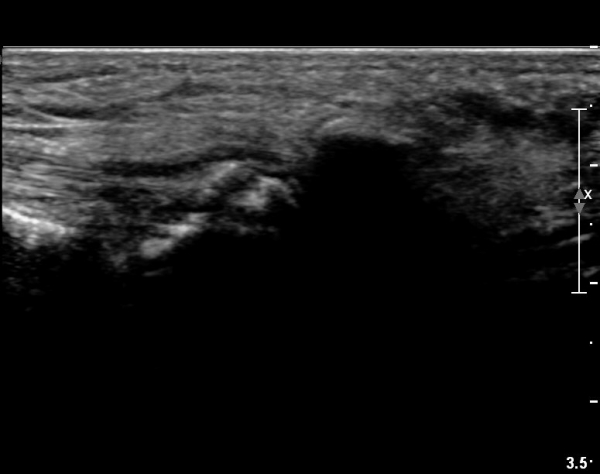

ÃÊÀ½ÆÄ °Ë»ç

±¹¼ÒÀû ¾ÐÅëÀ» º¸ÀÌ´Â ÁßÁ·°ñÀÔ¹æ°ñ °üÀý ¹Ù´ÚÃø¿¡ ŽÃËÀÚ¸¦ ´ë´Ï Á¾ÀÚ»ÀÀÇ °¡ µÎ Á¶°¢À¸·Î

°üÂûµÇ°í Á¾ÀÚ»À ±ÙÀ§ºÎ¿¡ Àú¿¡ÄÚ ¿¬ºÎÁ¶Á÷ ºÎÁ¾ÀÌ °üÂûµÇ°í µÎ Á¾ÀÚ»À »çÀÌÀÇ »À Ç¥¸éÀÌ °ÅÄ£

¾ç»óÀ» º¸ÀÓ(»çÁø 1).

ŽÃËÀÚ¸¦ ¾à°£ ¾ÕÂÊ(¹ß ¿ÜÃø)À¸·Î À̵¿ÇÏ´Ï Á¾ÀÚ»À¿¡ ºÙ´Â Àåºñ°ñ°ÇÀÌ °üÂûµÇ°í °Ç ÁÖÀ§ ºÎÁ¾ÀÌ °üÂûµÊ(»çÁø 2, 3).

ŽÃËÀÚ¸¦ Á» ´õ ±ÙÀ§ºÎ·Î À̵¿ÇÏ¿© Àåºñ°ñ°ÇÀÇ Á¾´Ü¸é ±ÙÀ§ºÎ ¿µ»óÀ» È®ÀÓÇÔ(»çÁø 4)